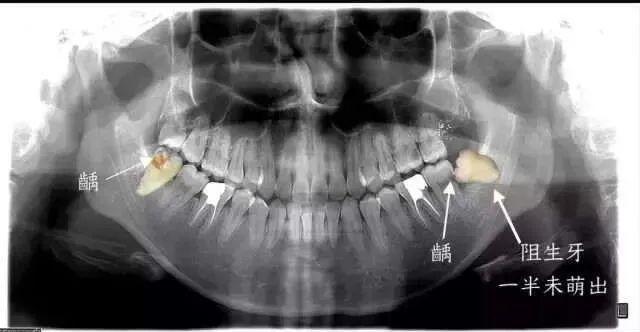

门诊病历显示,王奥纪自述智齿萌出后,反复发炎疼痛已有两个月,在“右下阻生齿萌出,要求拔除。”他否认有高血压、心脏病、糖尿病等病史。

从下图可见,这些是被拔去的相对完整智齿,而更多的智齿其实已经在拔牙过程中四分五裂。即便如此,这些幸存下来的智齿,或多或少也已经出现了各种龋损和破坏。